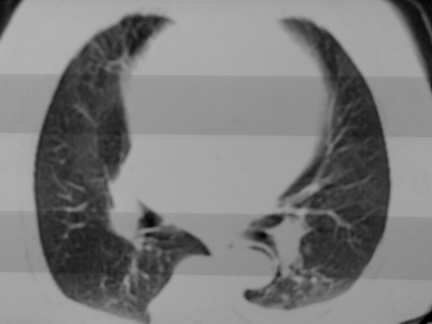

右肺炎性变

双侧胸腔积液

胸膜肥厚,

气管,支气管软骨钙化。

右肺感染;双侧胸腔少量积液,心影增大,可能与心功不全有关;胸内甲状腺肿。

胸内甲状腺肿;右肺感染;双侧胸腔少量积液。

胸内甲状腺肿;右肺中叶感染;双侧胸腔少量积液;心影增大,考虑有心功能不全。